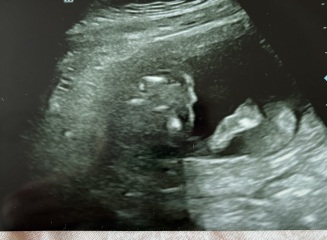

me and my partner recently had our 16 week gender scan. we were told the baby is a girl but i’m slightly paranoid!

baby was in awkward positions and the ultrasound tech told us she was getting different angles to get a definite answer for us!

i’ve attached our scan, would you say this is right for a girl?

gender scan